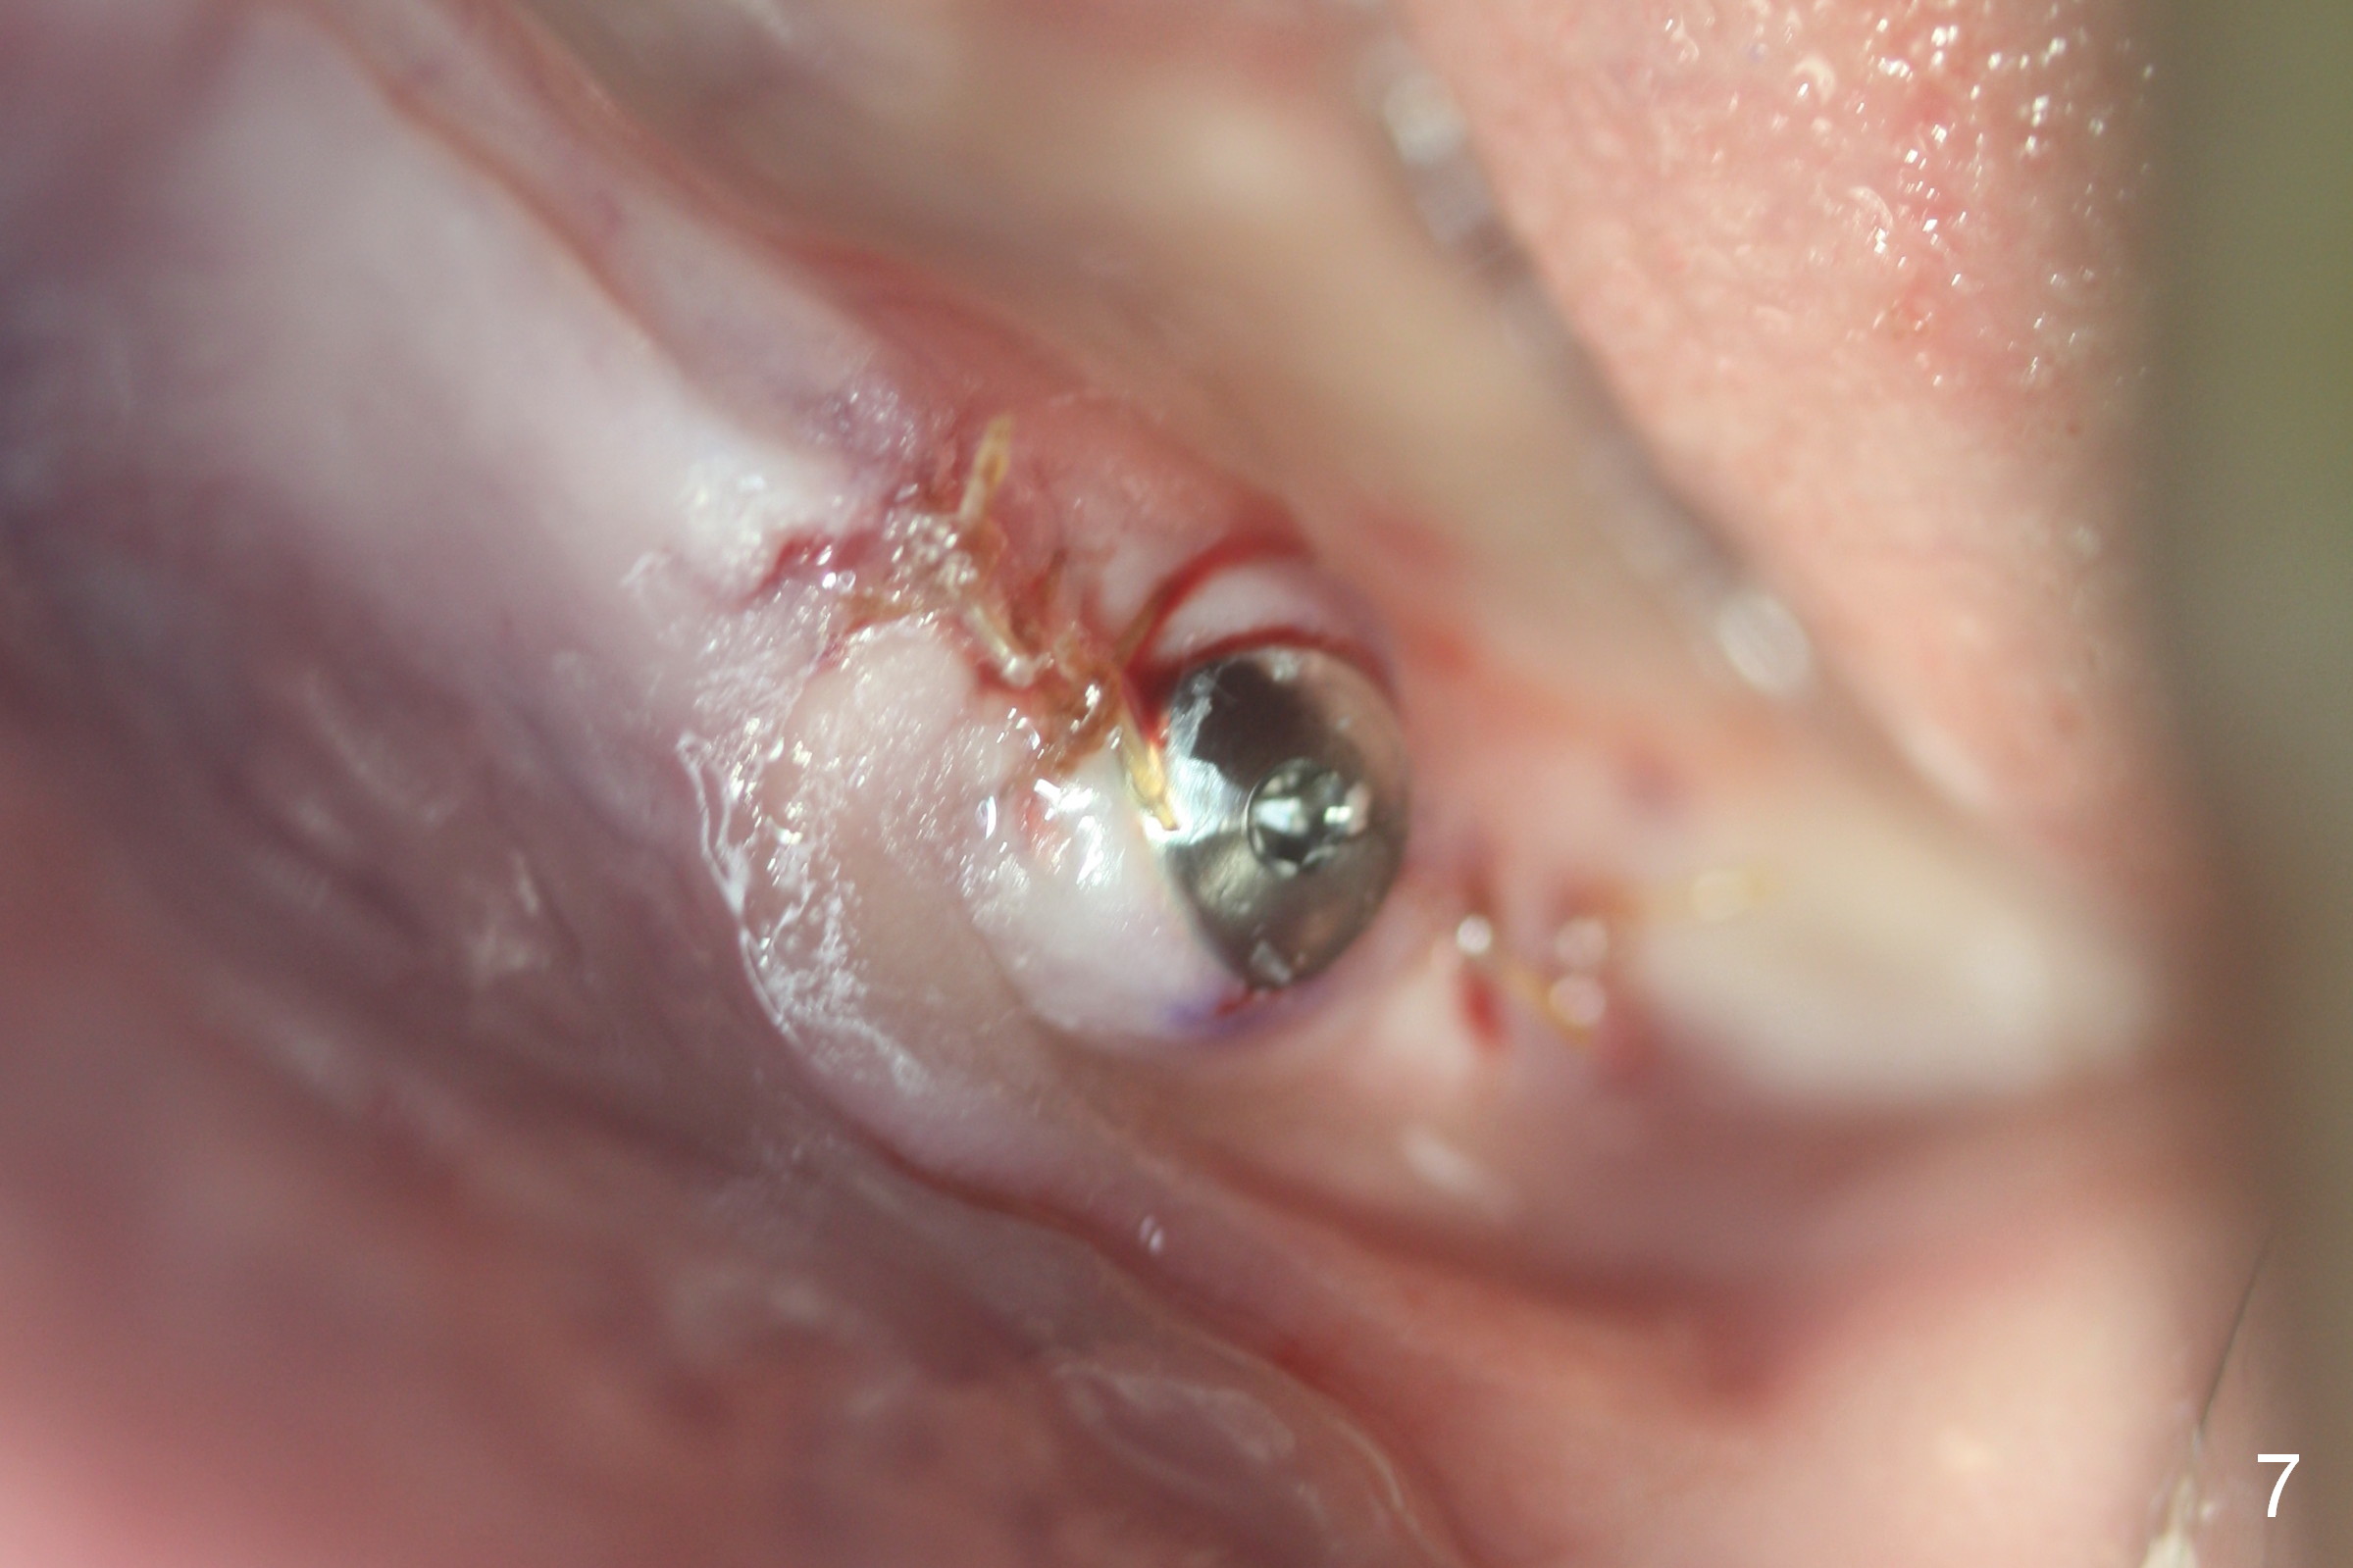

Except the tooth #30, the patient is completely edentulous (Fig.1,2). His chief complaint is "food gets into the missing tooth area". Due to short guide pin (Fig.3) and parallel pin (Fig.4), it is difficult to calculate precisely at the site of #19 the distance to the superior border of the Inferior Alveolar Canal (Fig.4 red dashed line). The clearance appears to be limited when a 4.3 mm drill is in place with 11 mm depth (Fig.5). Therefore an implant shorter than the last drill is placed (5x9 mm, Fig.6). Insertion torque is >50 Ncm. A 5x4(2) mm pair abutment is inserted temporarily to check occlusion with the opposing dentition (A). Finally a 5x2 mm healing abutment is placed with harvested autogenous bone placed between the implant and abutment (Fig.7). Before discharging the patient, the lower RPD is in place to check the position of the implant/abutment (Fig.8).